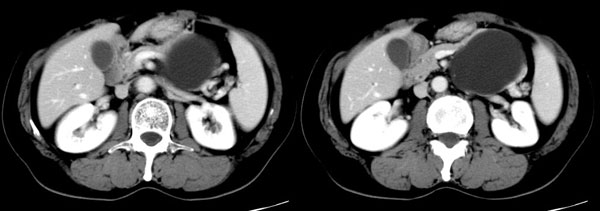

参照ct片,经皮穿刺,抽出透明液体60ml,随后置入引流管引流,囊液细胞学检查阴性,胰酶检查阴性。采用无水乙醇灌注治疗。4天后囊腔闭锁,无液体渗出,予以拔管。

置管后造影,显示囊腔直径约5cm,囊壁光整,正位、双斜位造影均未见造影剂外溢,与胰腺无交通